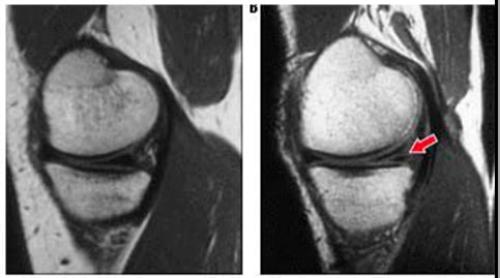

Степень повреждений мениска определяют посредством МРТ.

Чтобы в заключениях не было расхождений, врачи всего мира ориентируются на диагностические признаки состояния мениска по Столлеру (Stoller, американский ортопед, разработавший систему оценки):

- 0 степень – норма.

- 1 степень – патологические изменения (трещины) в толще тканей.

- 2 степень – большее количество изменений, но хрящ сохраняет форму.

- 3 степень – целостность тканей сильно нарушена, наблюдается разрыв.

Различные степени повреждения мениска по Столлеру. Нажмите на фото для увеличения